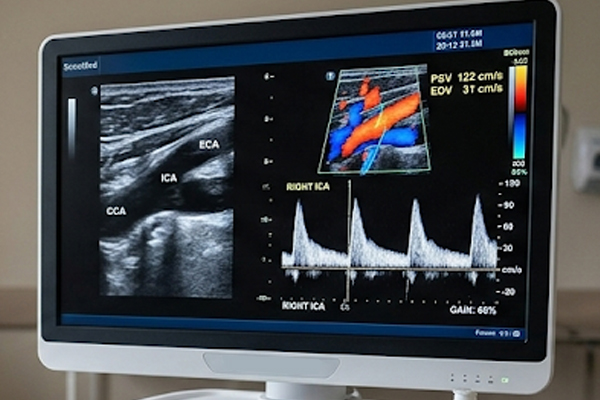

ECODOPPLER DE CARÓTIDAS E VERTEBRAIS COM FLUXO EM CORES

Outros nomes/mesmo exame: Ultrassom de carótidas e vertebrais com doppler colorido, Ecodoppler de carótidas, doppler de carótidas e vertebrais, duplex scan de carótidas e vertebrais.

É um exame relacionado ao estudo anatômico e funcional das artérias carótidas e das artérias vertebrais utilizando-se o ultrassom.

Estudo dos fluxos sanguíneos para o território cerebral.